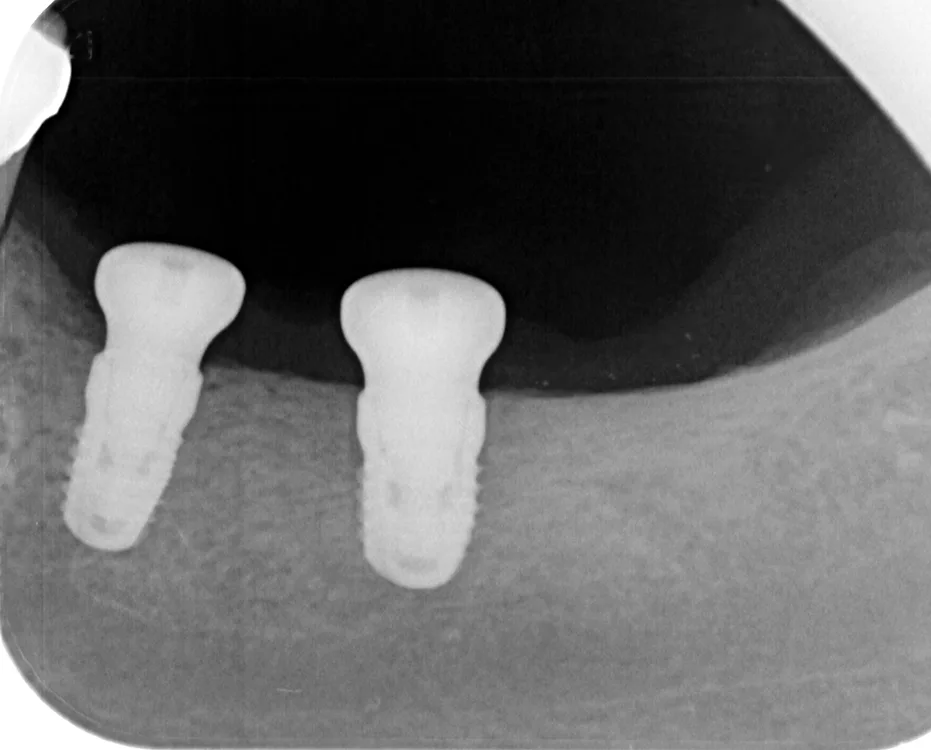

- Fortgeschrittene Alveolarkammatrophie im Unterkiefermolarenbereich (häufig) (Abb. 23 bis 29)

- Nähe zum N. alveolaris

Transversale Implantatknochenplateaus werden während der Implantation chirurgisch korrigiert (GOÄ 2730), um periimplantäre Trichter und prothetisch lange Abutments mit infektanfälliger Gingiva zu vermeiden (Abb. 30). Die prothetische Versorgung des Unterkiefers erfolgt festsitzend unter Verwendung axial verschraubter, nicht zementierter, unverblockter Einzelkronen (Hygiene, Zementierungsschäden, Periimplantitis). Die Integration in den Praxisalltag gelingt nur mit Fokus auf die Gewebebiologie unter Abkehr von der rein mechanistischen Versorgungslehre und Verblockungstheorie.